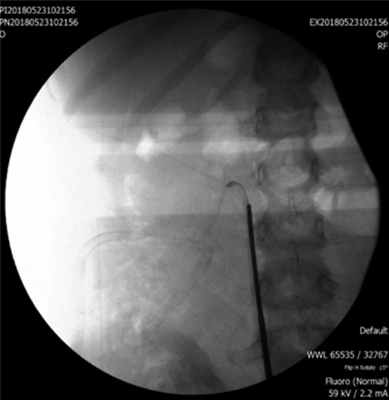

Это свидетельствовало о том, что у ребенка, вероятно, очень редкий вариант изолированного отрыва мочеточника от ло-ханки без критического повреждения сосудистой ножки. Данное обстоятельство требовало уточнения, поэтому выполнили уретероскопию и ревизию дренирующей системы. Ригидный уретероскоп провели через устье правого мочеточника. Последний был сужен, аперистальтичен, содержал большое количество хлопьев и взвеси. На уровне нижнего края II поясничного позвонка выявлена полная облитерация просвета мочеточника (рис. 3). Рис. 3. Уретероскоп в правом мочеточнике, проведенный до зоны облитерации.